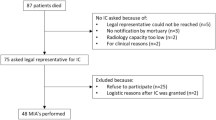

Ethical permission was obtained from the medical ethical committee Arnhem-Nijmegen (ClinicalTrials.gov identifier: NCT04596943). All study proceedings were performed in accordance with Dutch clinical trials guidelines and all participants provided written informed consent prior to participation. In this single-center proof-of-concept prospective observational study, we included hospitalized adult patients with PCR proven SARS-CoV-2 infection, admitted to the nursing ward. Exclusion criteria included previously documented severe lung abnormalities, glomerular filtration rate ≤ 30 ml/min, contra-indications for PET/CT (pregnancy, breast-feeding or severe claustrophobia) or contra-indications for administration of iodine-containing agents. Patient data, including demographics, medical history, clinical parameters, laboratory examinations, treatment and complications during hospital stay were collected. No adverse events were reported.